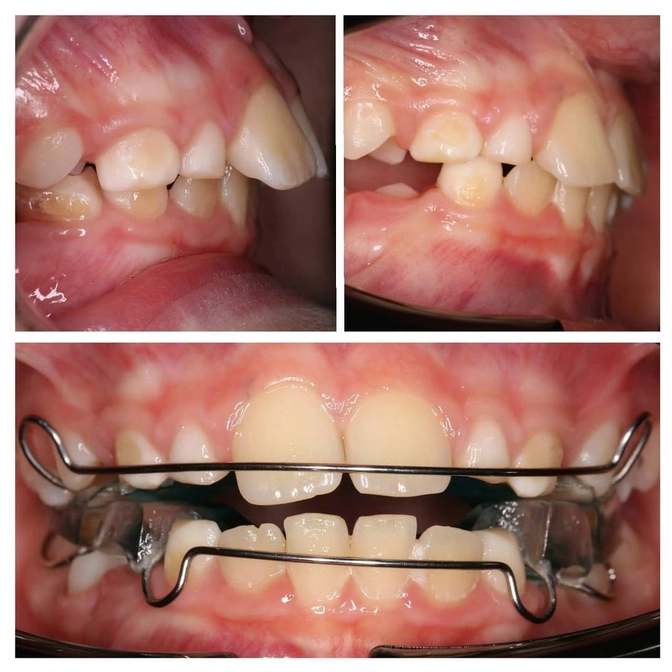

Аппарат Твин-Блок: клинический случай.

У пациента дистальный прикус и протрузия резцов на верхней челюсти.

Ортодонт нашей команды Диана Кива назначила пациенту лечение аппаратом твин-блок.

И такого крутого результата они достигли ВСЕГО ЗА 3 МЕСЯЦА!